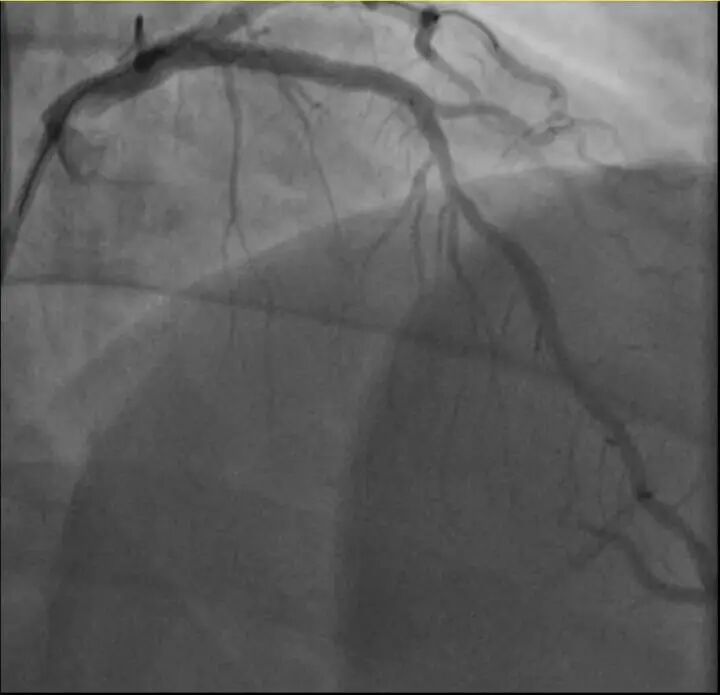

介入治疗后影像图

浙江医院心血管内科的医生分析,剧烈运动导致这位患者心脏的不稳定斑块破裂,进而造成前降支近段次全闭塞。所幸送医及时,孙先生的身体险情被化解。